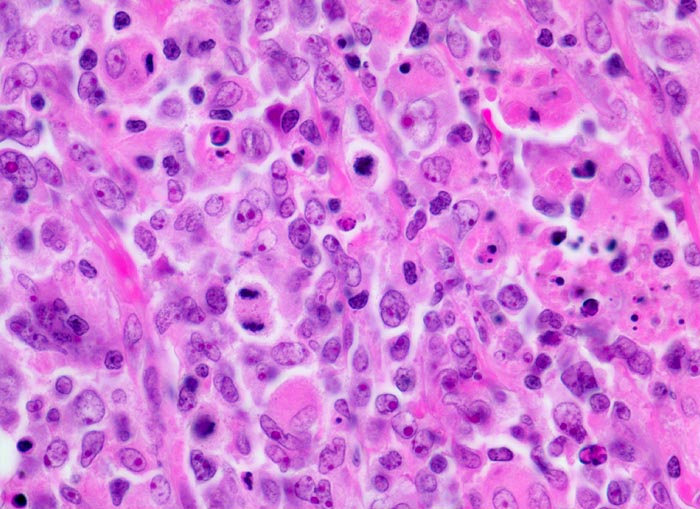

Diffuses grosszelliges B-Zell Lymphom

Lymphknoten, abdominal

Mittelgrosse stark polymorphe Tumorzellen mit unregelmässig geformten, teils lobulierten oder eingekerbten Kernen. Oft sind mehrere randständige Nukleolen erkennbar (Zentroblastische Variante). Schmaler Zytoplasmasaum. Zahlreiche Histiozyten mit reichlich eosinophilem Zytoplasma und ovalen Kernen ohne Atypien. Mehrere Mitosen und Apoptosen als Ausdruck der raschen Zellproliferation.

Magenlymphom mit Befall abdominaler Lymphknoten.

630